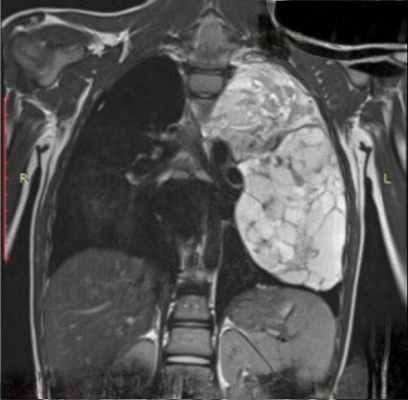

Магнитно-резонансная томография (МРТ).

Полная диагностика тимомы включает также современные диагностические исследования – КТ, МРТ, — которые позволяют получить точные данные о расположении опухоли, ее размерах, распространенности патологического процесса и другую информацию, необходимую для подбора качественного лечения.

Одышка, кашель, болезненные ощущения в груди, отечность верхней половины вены из-за нарушения оттока крови, нарушения в работе иммунитета, в том числе слабость мышц, ночная потливость, субфебрильная температура — все это может быть признаками опухоли. На поздних стадиях наблюдается повышенная утомляемость, потеря аппетита и массы тела и другие проявления раковой интоксикации. Для установления диагноза наиболее информативным методом считается КТ с контрастированием, также могут использоваться рентгенография, МРТ, биопсия.